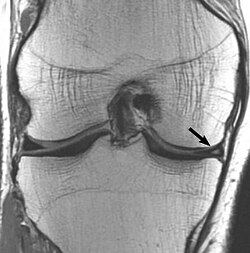

Knee with medial meniscus tear (bucket-handle type) showing displaced meniscal fragment, joint effusion, and...